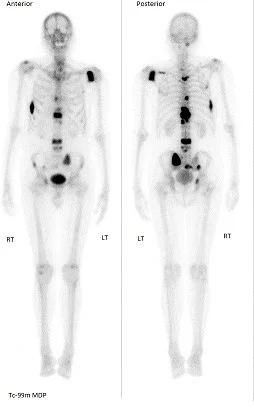

Bone Scan: Whole Body; Three Phase

Es un procedimiento de medicina nuclear que utiliza pequeñas cantidades de material radiactivo (radiofármaco) para obtener imágenes del esqueleto completo. Este radiofármaco se fija en áreas de los huesos con mayor actividad metabólica, lo que permite visualizar alteraciones que podrían pasar desapercibidas en estudios convencionales.

La modalidad de tres fases ofrece información detallada sobre:

• Flujo sanguíneo óseo (fase inicial)

• Distribución temprana del radiofármaco (fase intermedia)

• Captación tardía en los huesos (fase final)

Gracias a esta combinación, el estudio permite identificar de forma temprana fracturas ocultas, infecciones, inflamaciones articulares, tumores primarios y metástasis óseas, facilitando diagnósticos más rápidos y precisos en comparación con radiografías tradicionales.